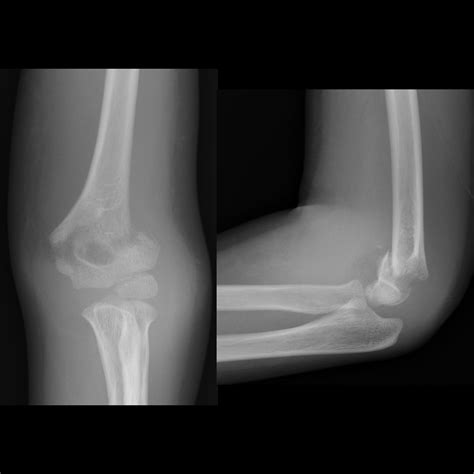

Diagnosing a Medial Epicondyle Fracture

Diagnosing a Medial Epicondyle Fracture involves a combination of physical examination and imaging tests. The diagnostic process typically includes:

• Physical Examination: The healthcare provider will assess the elbow for swelling, tenderness, and range of motion. They may also check for any deformities or instability in the joint.

• Imaging Tests: X-rays are the primary imaging tool used to diagnose a Medial Epicondyle Fracture. They can reveal the location and extent of the fracture. In some cases, additional imaging such as a CT scan or MRI may be required to provide a more detailed view of the injury.

Accurate diagnosis is crucial for determining the appropriate treatment plan.